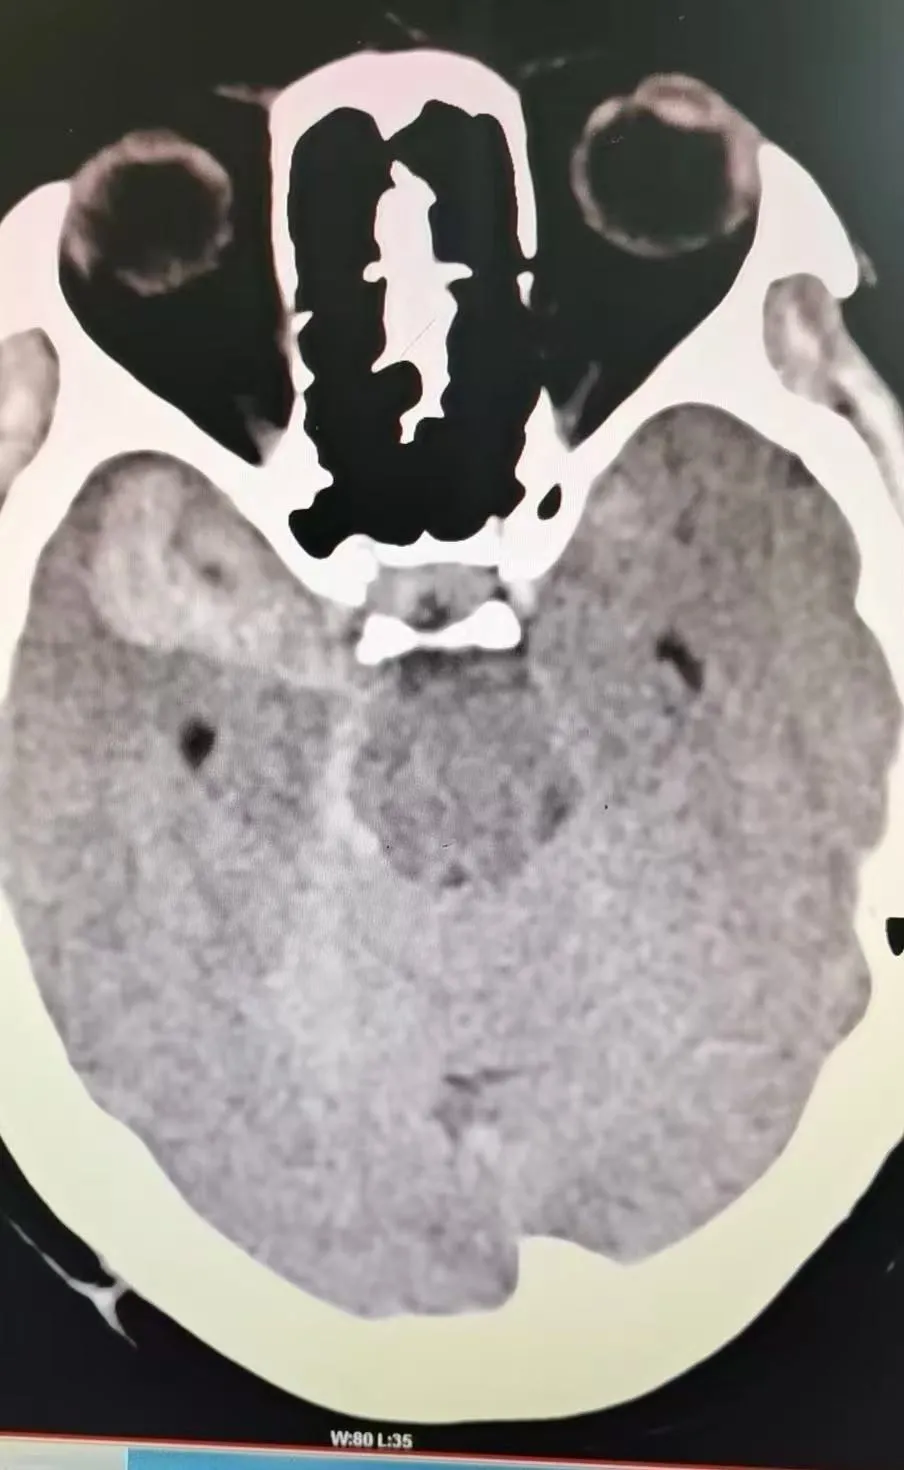

术前头部CT

患者张某某,女,58岁,因突发头痛头晕1小时入院。入院时神志昏睡,精神差,双侧瞳孔等大等圆,对光反射消失,颈部抵抗,四肢肌力检查不配合等。急查头部CT平扫,提示自发性蛛网膜下腔出血,右侧额颞叶硬膜下血肿,右侧颞叶脑内血肿。患者病情十分危重,紧急收住医院神经外科,予对症治疗后,患者病情逐渐好转,神志清醒。经完善头部CTA提示,右侧颈内动脉后交通动脉瘤并破裂出血,诊断为颅内动脉瘤破裂出血,建议其尽快进行手术治疗,开颅夹闭动脉瘤是颅内动脉瘤治疗的重要方式,安全性高,恢复快、预后佳。